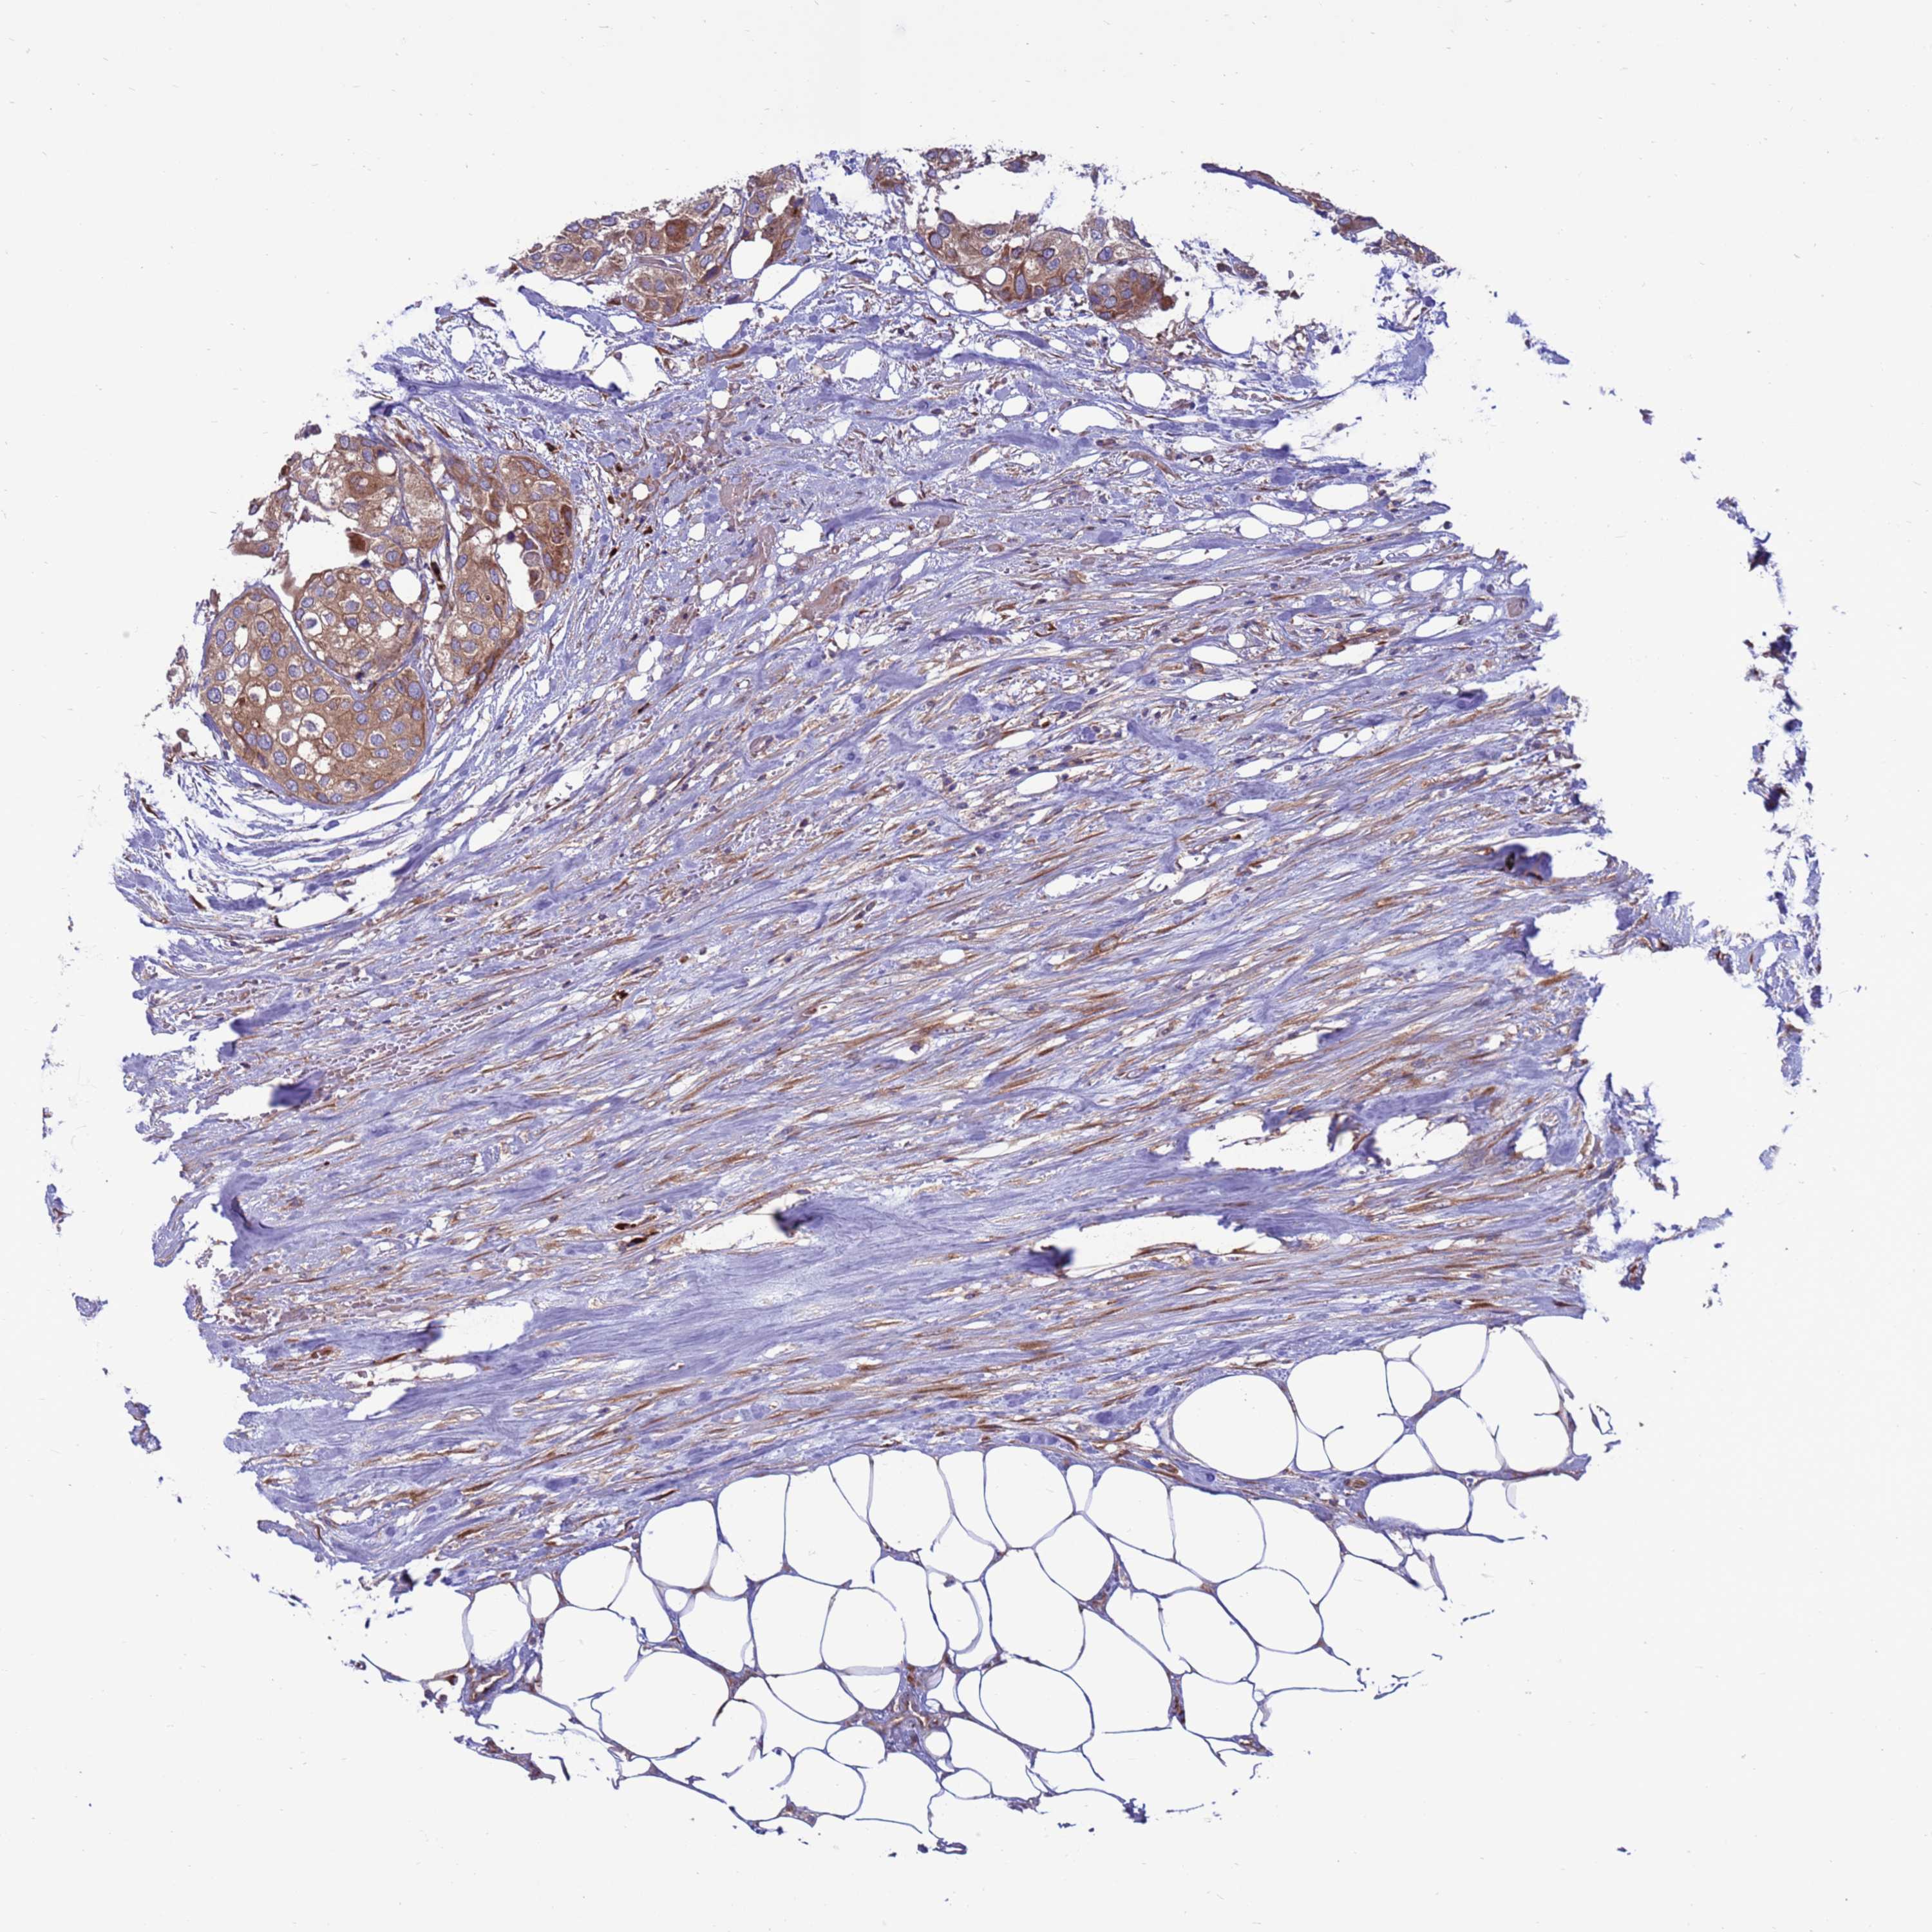

UROTHELIAL CANCER - Protein expressioni

A mouse-over function shows sample information and annotation data. Click on an image to view it in a full screen mode. Samples can be filtered based on level of antibody staining by selecting one or several of the following categories: high, medium, low and not detected. The assay and annotation is described here.

Note that samples used for immunohistochemistry by the Human Protein Atlas do not correspond to samples in the TCGA dataset.

Antibody stainingi

Antibody staining in the annotated cell types in the current human tissue is reported as not detected, low, medium, or high, based on conventional immunohistochemistry profiling in selected tissues. This score is based on the combination of the staining intensity and fraction of stained cells.

Each image is clickable and will lead to virtual microscopy that enables deeper exploration of all samples and also displays staining intensity scores, fraction scores and subcellular localization as well as patient and tissue information for each sample.

Antibody HPA047818

Staining

High

Medium

Low

Not detected

Intensity

Strong

Moderate

Weak

Negative

Quantity

>75%

75%-25%

<25%

None

Location

Nuclear

Cytoplasmic/membranous

Cytoplasmic/membranous,nuclear

Urothelial carcinoma, Low grade

Urothelial carcinoma, High grade